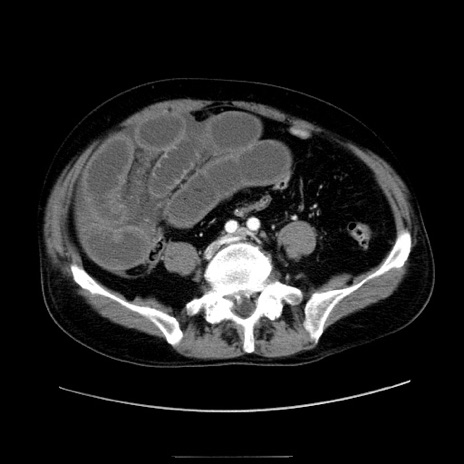

症例30(横断像)

【症例】80歳代男性

【主訴】臍周囲痛

【現病歴】約6時間前から臍下部痛が出現。次第に腹部膨隆・背部痛も生じてきたため来院。背部痛の場所は変化しない。

【身体所見】意識清明、BT 36.3℃、BP  131/87mmHg、P 87bpm、SpO2 100%(RA)、臍周囲自発痛・圧痛あり、反跳痛なし、自発痛部位に一致して板状硬あり、腹部膨隆、腸雑音減弱、CVA tenderness両側陰性。

【データ】WBC 19600、CRP 0.33